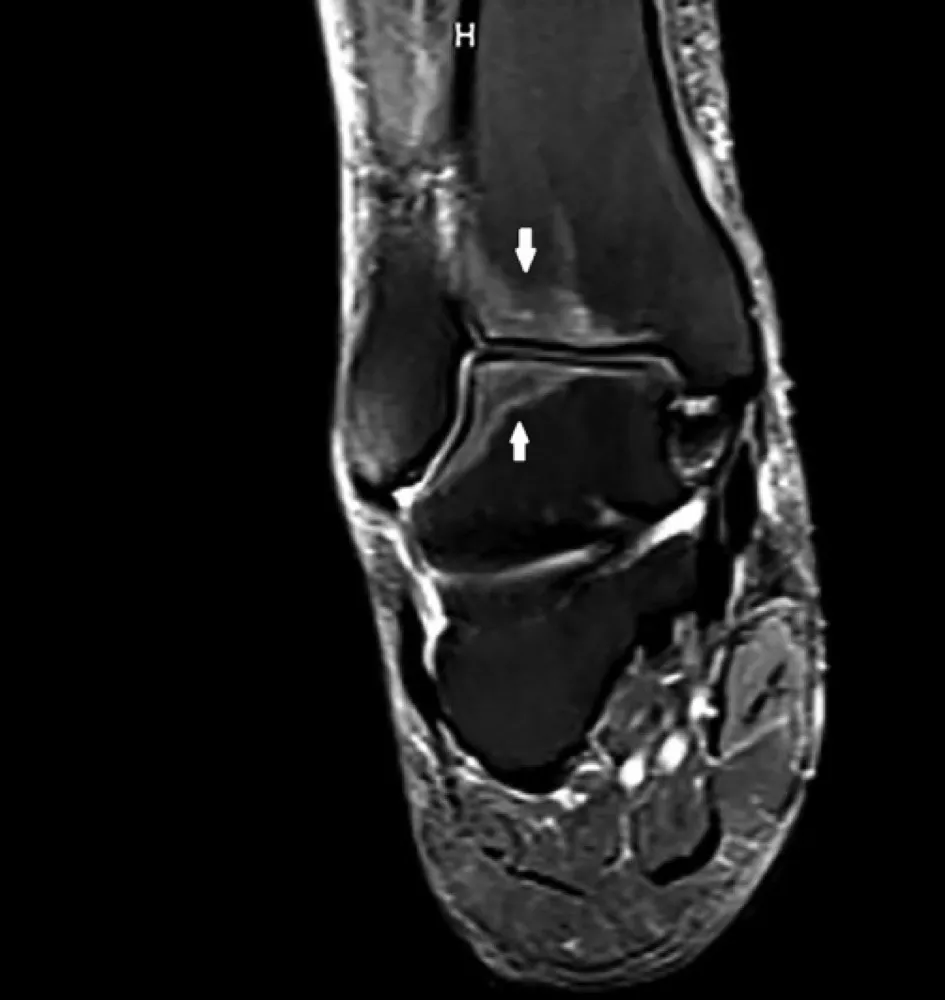

Uma causa incomum de hematúria glomerular intermitente!

Hematúria pós infecção, caso clínicos para auxiliar no entendimento de causas glomerulares comuns e raras...